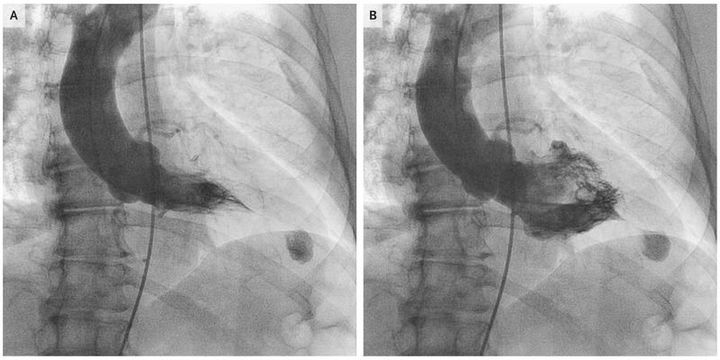

A 68-year-old woman presented with symptoms of palpitations and was found to have frequent premature ventricular contractions and nonsustained ventricular tachycardia. A transthoracic echocardiogram showed possible evidence of left ventricular apical aneurysm, and a left ventriculogram was obtained (Video 1). Hypertrophic cardiomyopathy with an apical variant was seen during systole (Panel A) and diastole (Panel B) and was subsequently confirmed on cardiac magnetic resonance imaging. The patient did not have angiographic evidence of epicardial coronary artery disease. Genetic testing was not performed. She was treated with sotalol for the palpitations and received an implantable cardioverter–defibrillator (ICD) for primary prevention of sudden cardiac death. At a clinic visit 5 months later, she had received no ICD shocks and reported no symptoms of severe palpitations. The apical variant is seen more frequently in the Asian population than in the non-Asian population (which included the patient, who was white). Longitudinal cohort studies have shown that the rate of cardiac death among patients with apical hypertrophic cardiomyopathy is similar to that among patients with other forms of hypertrophic cardiomyopathy but is higher among women than among men.